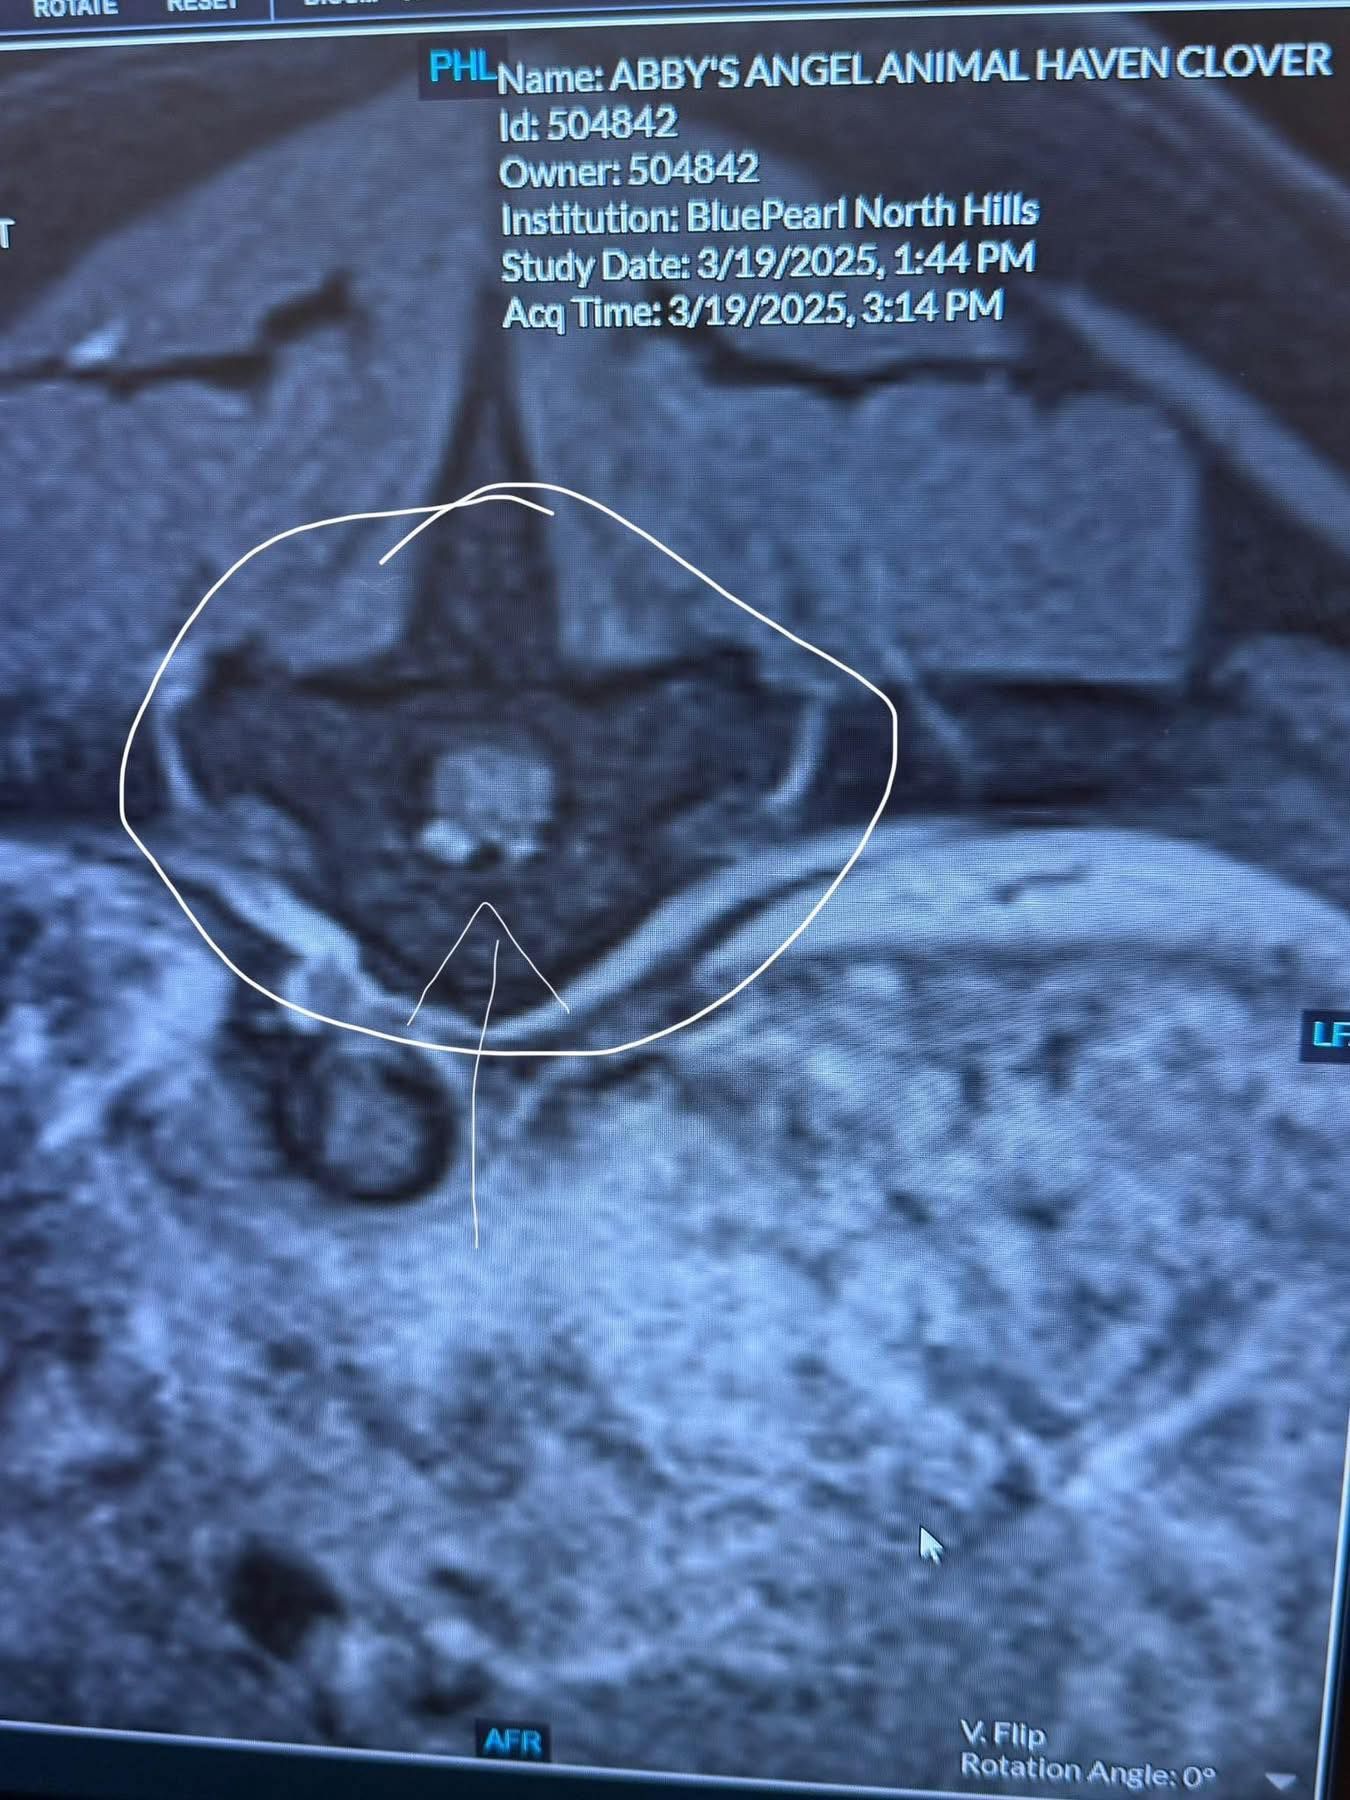

Clover has a tumor around her spinal cord, between T11 & T12 vertebrae. Basically right in the middle of her spine. In the MRI photos below, the third photo shows normal spinal cord looking at it as though you sliced into a pumpkin roll. The fourth photo shows the area the tumor is compressing on her spine. The fifth photo is the tumor itself.

Her spinal tap didn’t provide much additional information, but the best guess currently is that it is malignant, and is a plaque meningioma.